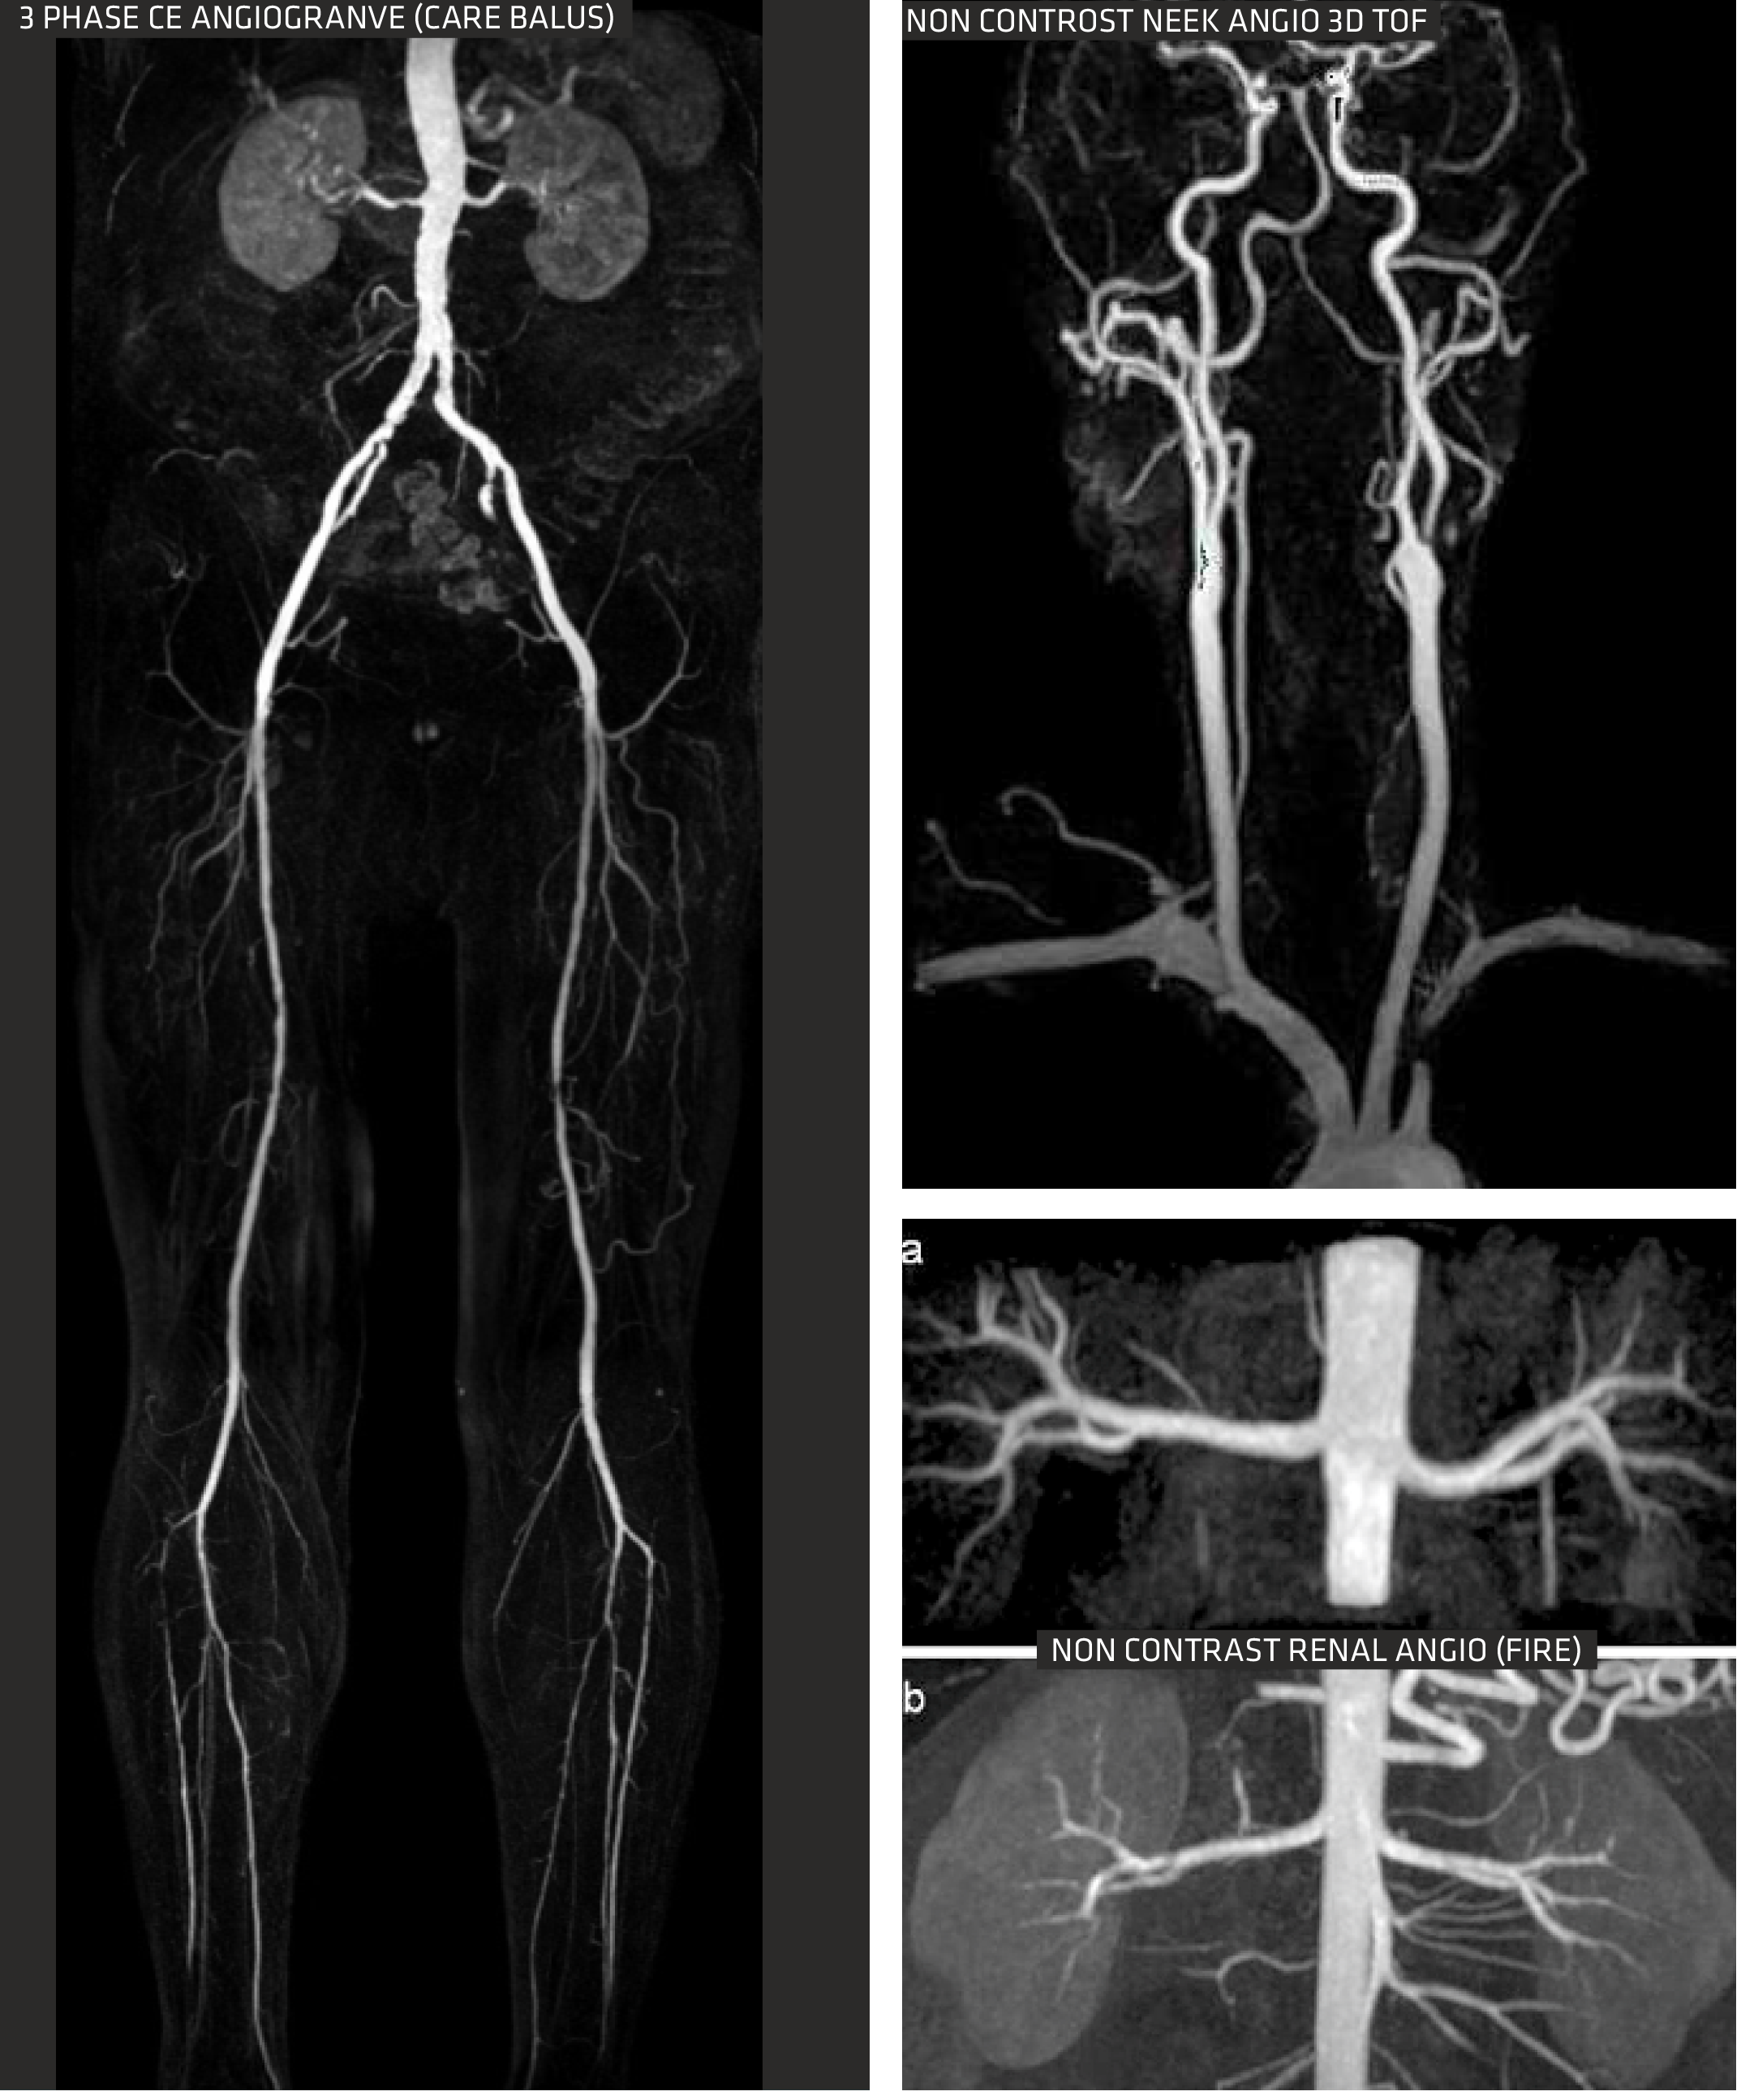

MUSIC 66X16 With all applications

Clarity 1.5T meets all your diagnostic needs with new generation quantitative tools and applications. Our advanced MUSIC technology allows for faster image acquisition and multiple exams without frequent user intervention.

MUSIC (Multi-Segment Imaging Combination) improves MR imaging with flexibility, precision, and speed. It utilizes an array of 66x16 RF channels that run simultaneously in one scan and FOV, hence enabling faster scans. You are required to choose the examination you want, without the need for coil replacement, which improves workflow and increases productivity. With MUSIC, repositioning patients for multiple exams is no longer necessary. Leveraging MUSIC's heightened precision allows us to image small lesions in a whole-body scan

Flexibility easy to use with more adaptability and versatility. You only need to choose the examination you want without the need for coils replacement, which improves workflow and increase productivity.

Precision With excellent and pinpointed precision, MUSIC provides excellent images quality from small lesions of the whole body

Speed: With MUSIC, the examination set-up is faster and simpler, and acquisition time is shorter. Increasing your patient through put.

Advanced Body imaging

The Sequoia Healthcare Clarity 1.5T oers comprehensive body imaging solutions with advanced tools tailored for patients. Its Free Breathing (ARCUS) MR Imaging protocols primarily utilize either breath-holding techniques or respiratory gating to eectively minimize motion-related artifacts, ensuring clearer and more accurate imaging results.